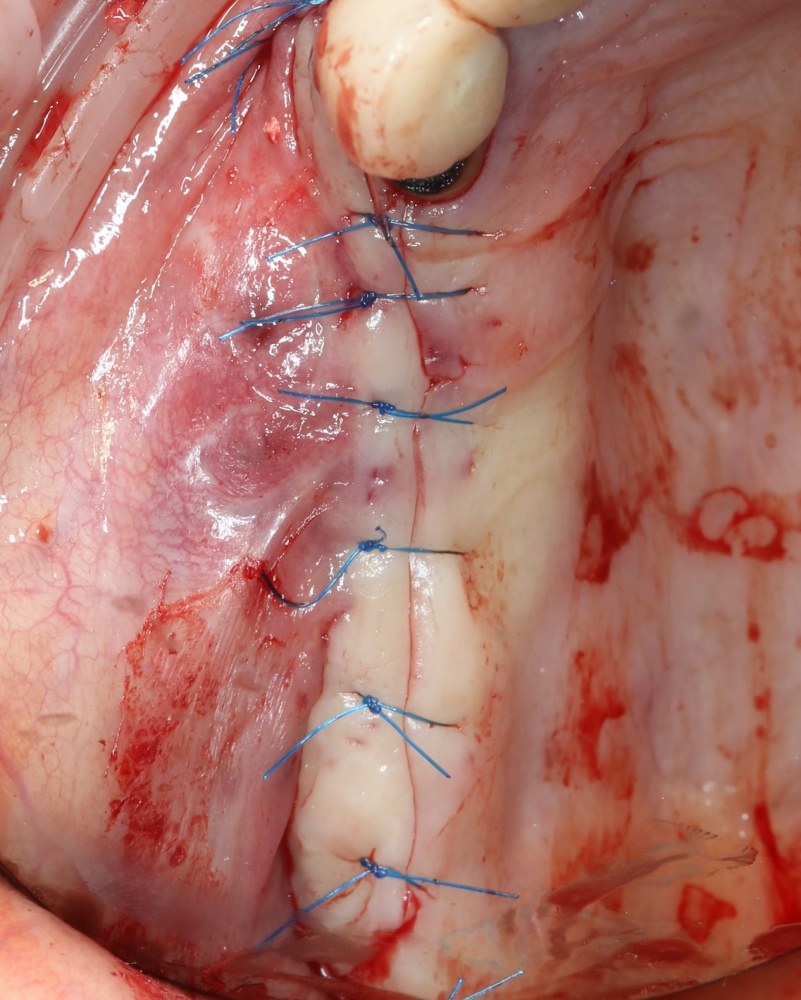

Синуслифтинг одномоментно с установкой имплантов.

Тут всё ясно и понятно. Разрез делается таким образом, чтобы удобно было поставить, в первую очередь, имплантаты, затем продляется на вестибулярную часть альвеолярного гребня для проведения синуслифтинг. Важную роль в этом играют вертикальные послабляющие разрезы и их длина:

Напомню, что подвижная слизистая оболочка может легко растянуться на 70% от своей первоначальной длины. Поэтому, моделируя вертикальный послабляющий разрез, рассеките, для начала, только кератинизированную часть десны. Обычно даже этого хватает. Далее, рассекайте подвижную слизистую оболочку по мере необходимости, пока не получите нормальный доступ к вестибулярной стенке верхней челюсти.